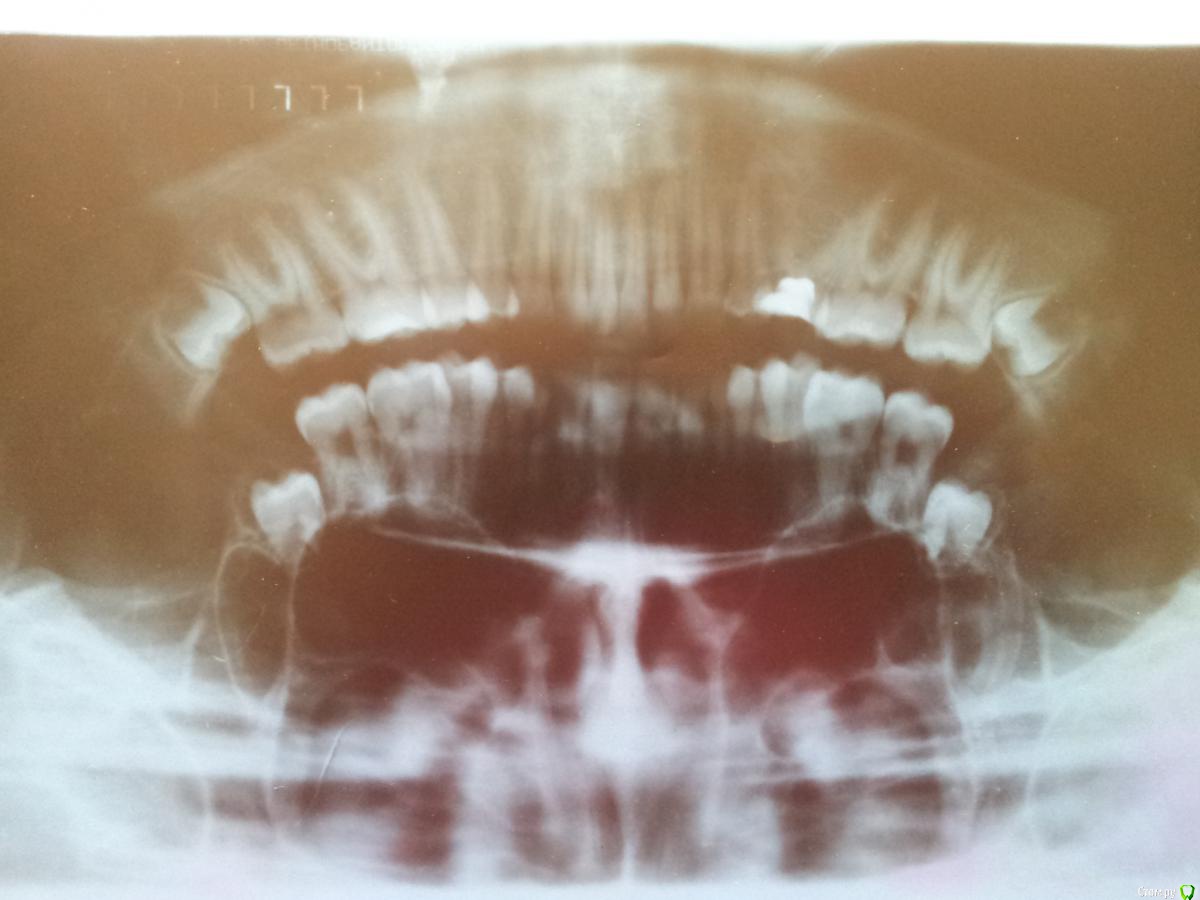

МИрина Опубликовано 25 февраля, 2015 Поделиться Опубликовано 25 февраля, 2015 Добрый день!Моей дочери 16 лет. Перед началом ортодонтического лечения нам назначили удаление нижних восьмерок. Обратились в детскую клинику, где нам составили план лечения. Посмотрев наш снимок, хирург стал настаивать на удалении только с глубокой седацией и только двух зубов сразу ( хотя мы хотим второй удалить позже, через месяц,- нам так наш ортодонт посоветовал). Причем, удаление двух зубов займет по расчетам хирурга 3 часа. Скажите, пожалуйста, действительно ли у нас такой сложный случай, что седация обязательна, неужели действительно по 1,5 часа на зуб? Дочь не боится удалять и наоборот отказывается делать под седацией. Не знаю, как поступить. Возможно, она переоценивает свои возможности, и надо ее уговаривать все-таки на глубокую седацию. Мы собираемся удалять пока один зуб. Прошу Вашего профессионального мнения: сколько по времени(хотя бы приблизительно) занимает удаление одной такой восьмерки? Спасибо. Ссылка на комментарий

faity Опубликовано 25 февраля, 2015 Поделиться Опубликовано 25 февраля, 2015 вам нужно 4 восьмерки удалять, по два за раз- имеется ввиду с одной стороны, седация не обязательна, если только сразу все 4 убирать, и то не факт. времени на два нужно максимум час, с условием того что на анестезию суммарно 15 минут и на ушивание лунок 10я бы не стал 16-летнего ребенка седацией травить Ссылка на комментарий

SDC Опубликовано 25 февраля, 2015 Поделиться Опубликовано 25 февраля, 2015 Вообще можно все 4 восьмых за 2 часа удалить. С седацией или нет - не имеет значения. Седация - для комфорта пациента.Непонятны рекомендации ортодонта - о последовательном удалении 8-х.Я тоже за одномоментное удаление по причине одного послеоперационного периода и возможно, однократного курса общей АБ-профилактики. 3 Ссылка на комментарий